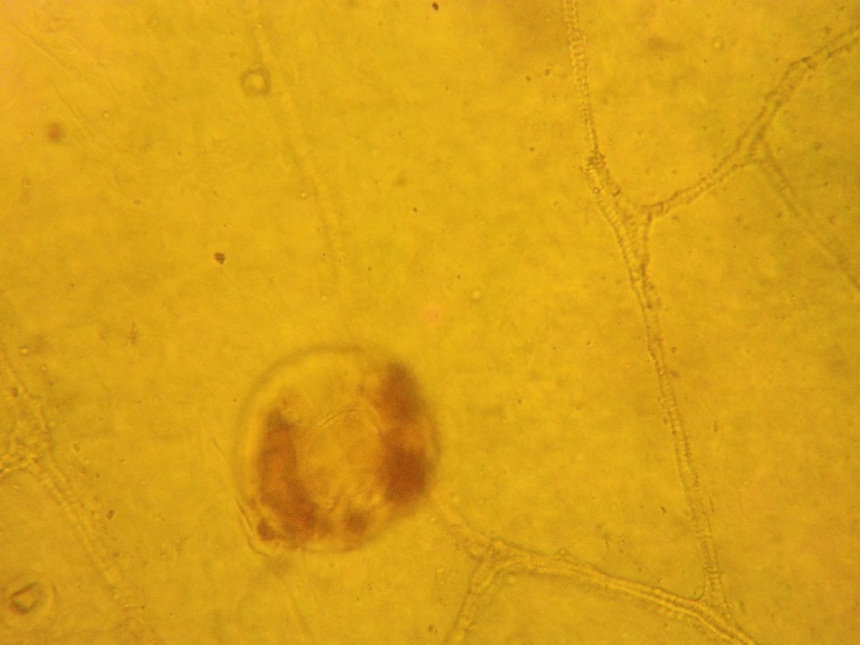

При микроскопическом исследовании препаратов листа с поверхности обнаруживаются простые многоклеточные волоски с бородавчатой кутикулой и головчатые волоски с одноклеточной ножкой и обратнояйцевидной одноклеточной головкой. Устьица диацитные. По поверхности в углублениях видны многочисленные эфирномасличные железки (рис.4). Эпидермис извилистостенный (рис.3). [1]

Рис.3. Извилистые стенки эпидермиса

Рис.4. Эфирномасличная железка

- На основе проведенного микроскопического анализа были обнаружены диагностические признаки Мяты перечной (извилистые клетки эпидермиса, эфирномасличные вместилища) и Мелиссы лекарственной (клетки эпидермиса c извилистыми стенками, устьица аномоцитного типа, железистые волоски).